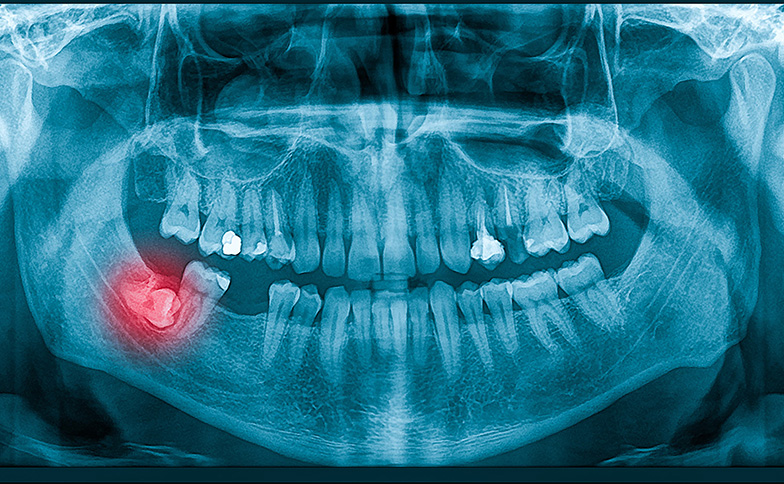

埋伏歯や親知らずの把握

レントゲンやCT画像は骨の中に埋まっている歯(埋伏歯)も正確に映し出します。例えば「親知らずが移動の邪魔になるので抜歯が必要」といった説明も、実際の画像を見ながら視覚的にご確認いただけるため、治療の必要性をしっかりと納得した上で進めていただけます。